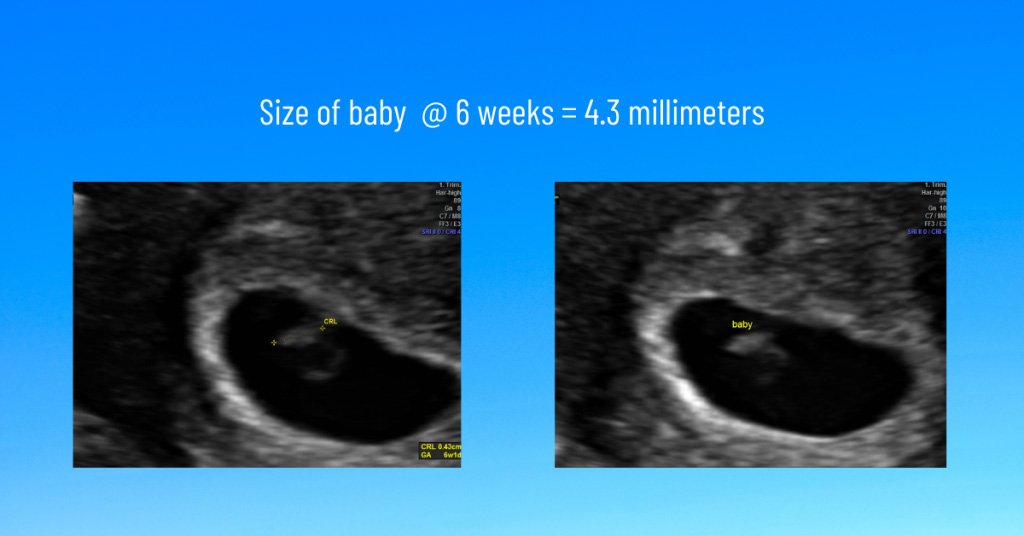

Is 6 weeks too early for ultrasound?

No, not if the calculated gestational age of the baby is correct. At 6 weeks, baby should have a visible heartbeat on ultrasound. Measurements can be taken, but may not be as accurate as a measurement taken at 9-12 weeks. Here at Wonder Time, we routinely help parents see a quick peek of their baby at 6 weeks. At this age, our typical scan lasts about 3 minutes, includes seeing the heartbeat, measuring the heart rate and measuring the length of the baby. During this delicate and rapid time of development, a quick peek is best. Baby is going to grow a millimeter every day for the next month or so!